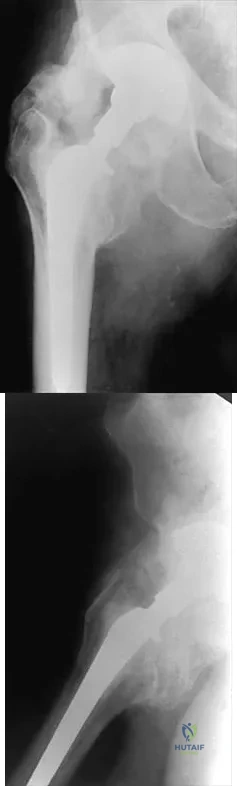

A 20-year-old man sustains the injury shown in Figures 1a and 1b in a motorcycle accident. In addition to a prompt closed reduction, his outcome might be optimized by

Figure 26 shows the radiograph of a 48-year-old woman who has right arm pain and hematuria. A bone scan reveals increased uptake in the left ribs and thoracic spine. A needle biopsy specimen shows that the lesion is highly keratin positive and composed primarily of clear cells. What is the best course of action?

A 26-year-old woman sustained a nondisplaced femoral neck fracture and treatment consisted of use of percutaneous cannulated screws. At her 3-month follow-up visit, she reports hip pain and is unable to ambulate. A radiograph is shown in Figure 1. What is the next most appropriate treatment?

What is the most likely long-term sequela of the injury shown in Figures 47a and 47b?